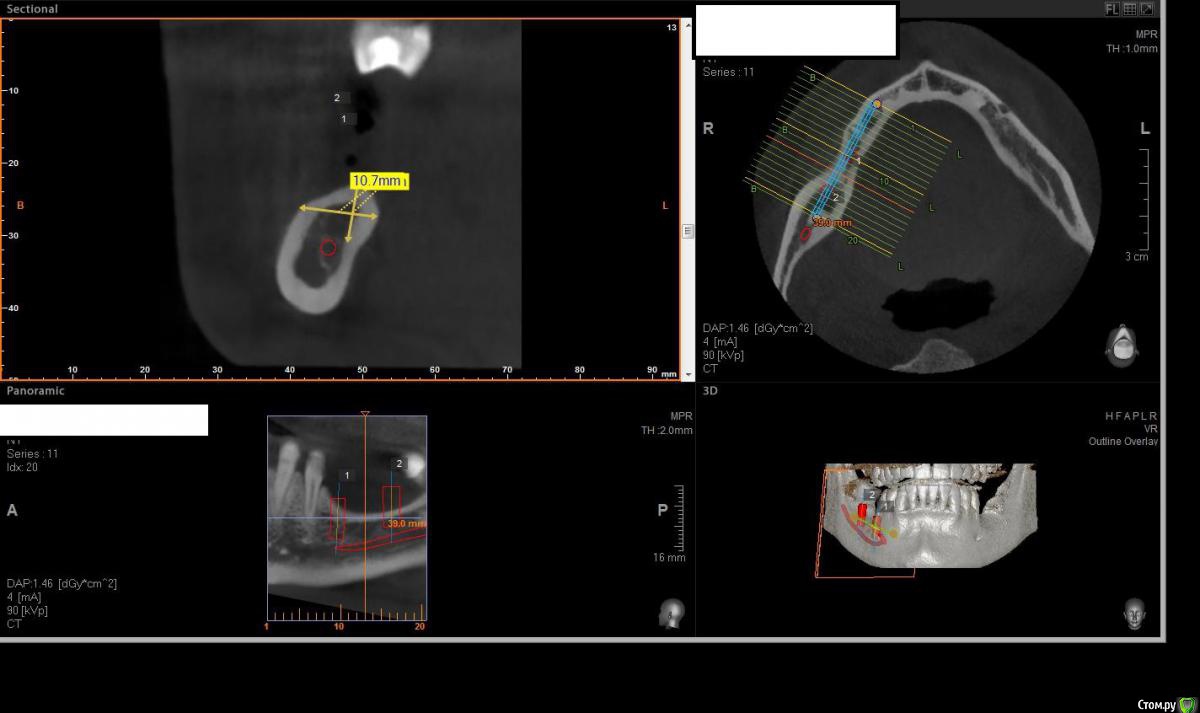

Павел7809 Опубликовано 21 ноября, 2017 Поделиться Опубликовано 21 ноября, 2017 Здравствуйте коллеги! Собственно ситуация на скринах. Для сосиджа как то экстремально большой объем. Блоки? Сетка?(ох как не хочется! последняя развалилась....) Крыша гаража? Из инструментария есть абсолютно все... Ссылка на комментарий

Павел7809 Опубликовано 21 ноября, 2017 Автор Поделиться Опубликовано 21 ноября, 2017 Коротышки с десной не рассматриваете? с удалением 8киинтересная идея...в принципе 2 астры туда влезают 4 на 6, боюсь просто эстетически получится некрасиво Ссылка на комментарий

Павел7809 Опубликовано 21 ноября, 2017 Автор Поделиться Опубликовано 21 ноября, 2017 Платформы имплантов будут на уровне апексов соседних зубов. Это будет эстетический ад. Ссылка на комментарий

Чертков Александр Опубликовано 22 ноября, 2017 Поделиться Опубликовано 22 ноября, 2017 Горизонтальная остеотомия здесь не пойдет, форма гребня не располагает. Сетка или Цитопласт. Ну или 3Д по Кури...если владеете. Безусловно с удалением 8го. Короткие импланты в данной ситуации я бы не стал использовать. 3 Ссылка на комментарий

Павел7809 Опубликовано 22 ноября, 2017 Автор Поделиться Опубликовано 22 ноября, 2017 (изменено) Да, но проблема в том , что на место 7 ки как бы и 6мм не влезает. Вообще мысль появилась поставить короткую 6 ку на месте 6 го зуба, удалить 8, поставить на его место имплант(там с местом проблемы нет, и сделать мостик) . Ну или сетка(ой как не хочется!) Мало того я посмотрел и понял что элементарно влезают восьмерки в обл 36 38 Изменено 22 ноября, 2017 пользователем Павел7809 1 Ссылка на комментарий

Павел7809 Опубликовано 25 ноября, 2017 Автор Поделиться Опубликовано 25 ноября, 2017 Пообщался с пациентом. Сошлись на коротышках 4 на 6 в область 7 ки, 9 на 4 в области 6 4ки. Да и по факту я посмотрел - коронки не будут такими уж огромными выглядеть. 1 Ссылка на комментарий